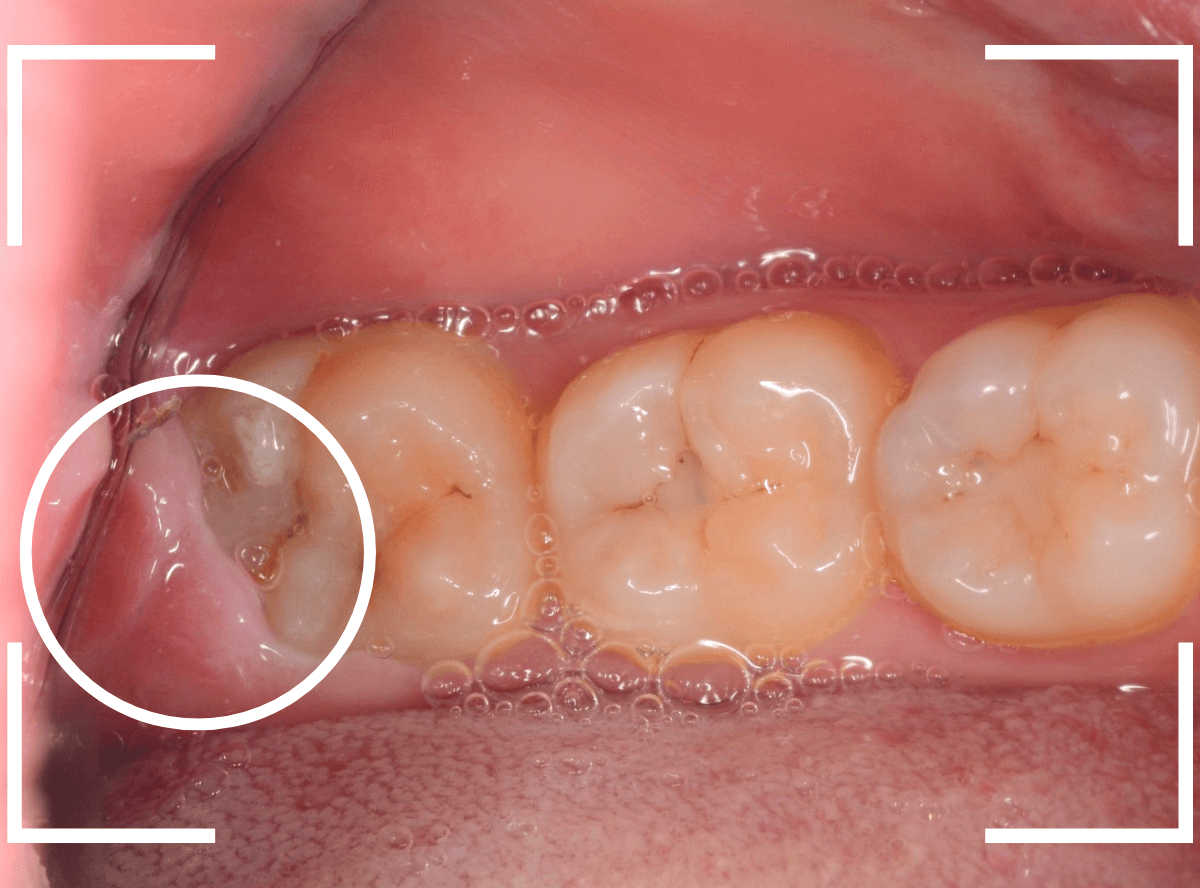

ここでは、比較的簡単なおやしらずの抜歯の例を中心にご紹介します。

このようなおやしらず、あなたはありませんか?